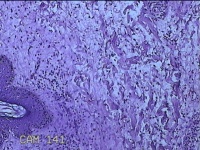

左侧会阴部结节

性别

女

年龄

43岁

临床诊断

皮肤良性肿瘤

一般病史

发现右侧会阴部结节3年余。

标本名称

大体所见

灰白粉红色带皮肤结节0.8x0.7x0.3cm一个,表面光滑,切开结节呈实性,切面灰白粉红色,质韧。